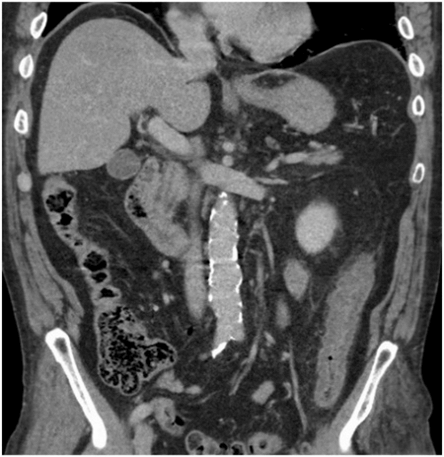

CT abdomen and pelvis with contrast showed non-specific colitis of the descending colon. Coronal and axial cuts are shown in (Figures 3 & 4). Following this, he underwent a sigmoidoscopy that showed a large mass-like ulcerated lesion in the descending colon. This involved about 15 cm of the colon and occupied about 30% of the lumen, as shown in (Figure 1). Histology was suggestive of ischaemic colitis (Figures 5-8). The multidisciplinary meeting recommended an interval colonoscopy which showed resolution of the colonic mass lesion (Figure 2). He was fluid resuscitated and started on empiric broad-spectrum antibiotics.

Figure 3: Coronal post-contrast abdominal CT.